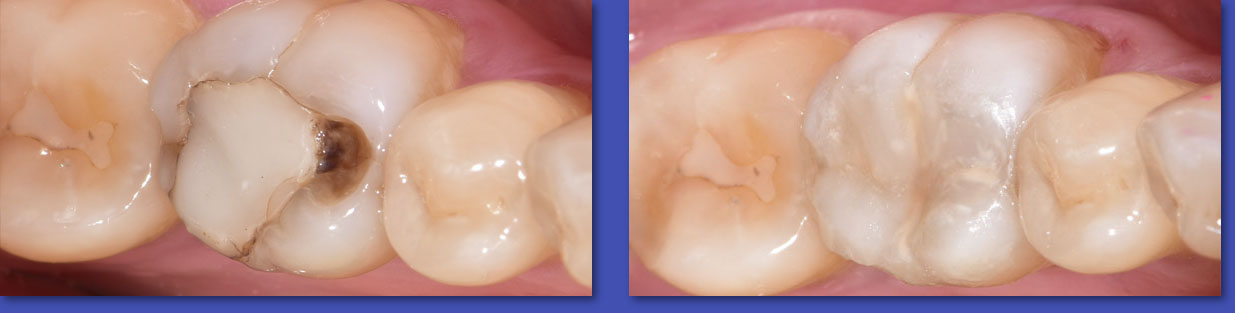

3. ENDODONCIA

La Endodoncia o tratamiento de conductos se encarga del tratamiento de las enfermedades que afectan al tejido pulpar del diente (también conocido como “ nervio” ).Gracias a éste tratamiento se puede preservar dientes que antiguamente había que extraer . La endodoncia se indica en casos de caries muy profundas ( lo más común ),dientes fracturadoso por indicación protésica.

Endodoncia o tratamiento de conductos